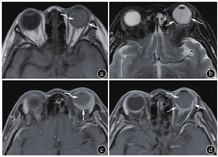

①单眼或双眼受累。②单灶或多灶:其中多灶包括单眼多发或双眼同时受累的病灶。③部位:肿瘤主体所在位置,分为眼球后极、后极偏侧及赤道部。多发病灶时记录较大病灶所在部位。④形态:新月形、半月形、梭形、不规则形。具体见图1。多发病灶时记录较大病灶的形态。⑤边界:主要观察病灶内侧缘,清楚或模糊。多发病灶时记录较大病灶的边界。⑥最大厚度:在显示肿物的最大层面测量,多发病灶时测量较大病灶。⑦信号与强化特征:以同层眼肌作为参照,记录肿物于T1WI、T2WI或FLAIR序列信号(分为高或稍高、等、低、混杂信号),以及强化程度(明显、中等、轻度、无强化);强化均匀性(均匀、不均匀)。

注:图a~d分别为新月形、半月形、梭形与不规则形。